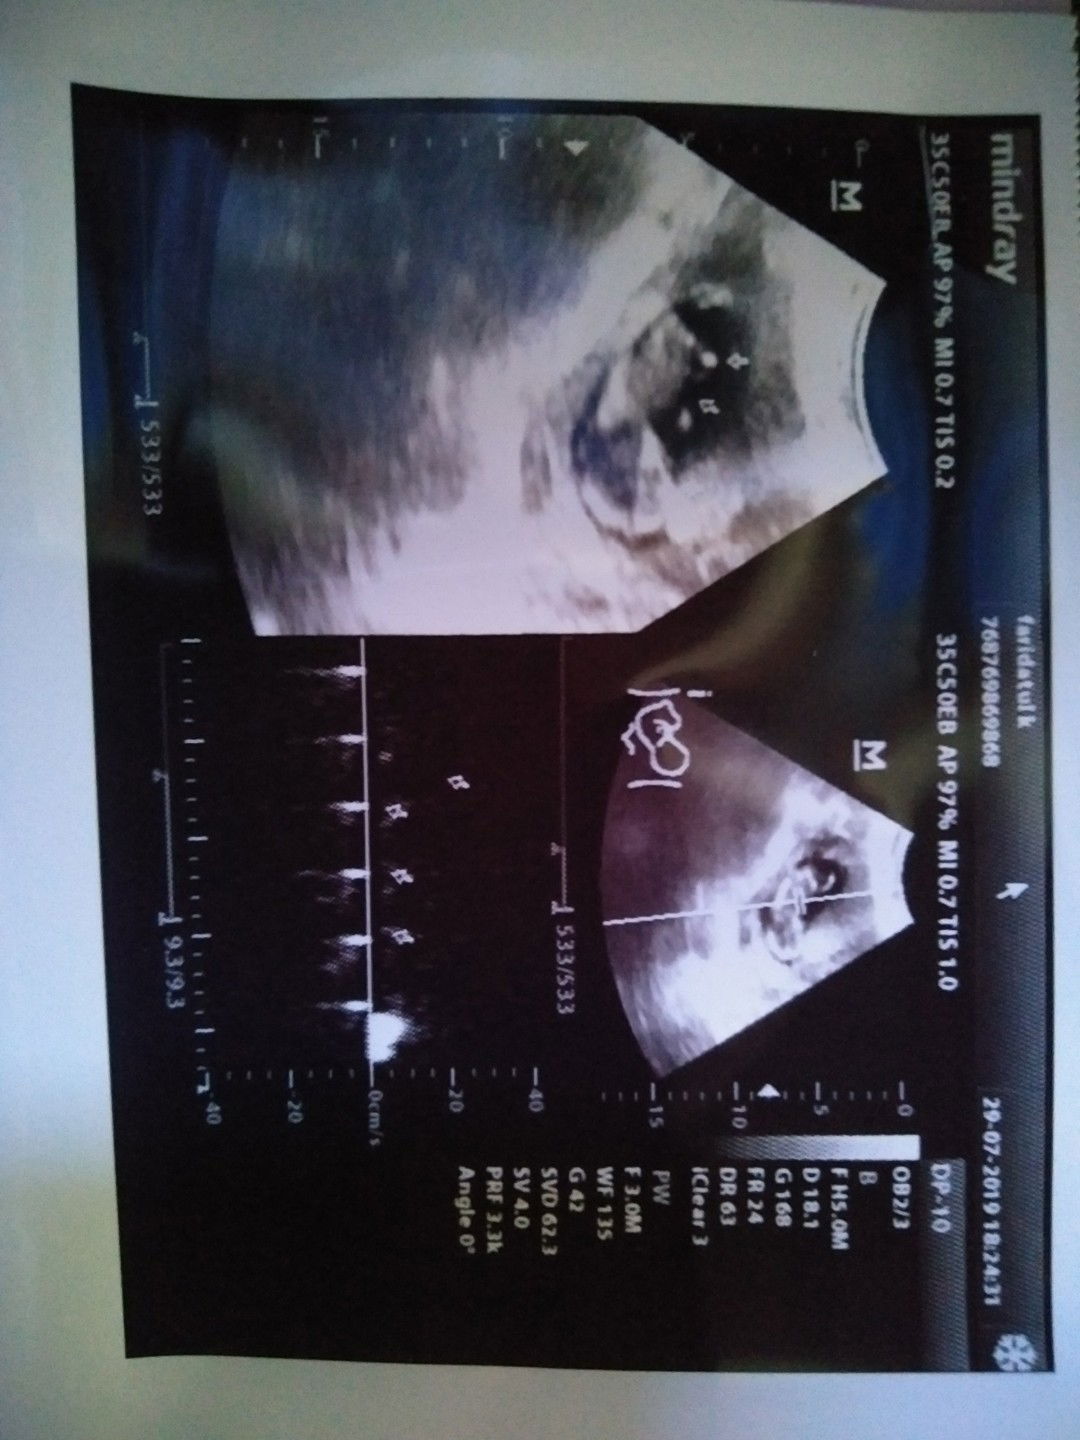

Bund msh ingt dgn sya yg usg di pusksmas tp ga jls kmrin..?? Sya maw berbgi kbhgiaan bund.. Ini sya usg di klinik hsilnya jlaz bgt..djj 166/mnit..bbjnya 80grm.. Debaynya aktf bgt..udh gerak2 wktu di usg.. Uk 13.week 2 day.. Alhmdullh..smpai trhru sya bund.. Smga bunda yg lg nunggu tiket h smga dsgrakn.. Yg lg hmil smga ibu dan debay sht smpai lhran nanti.. Aamiin